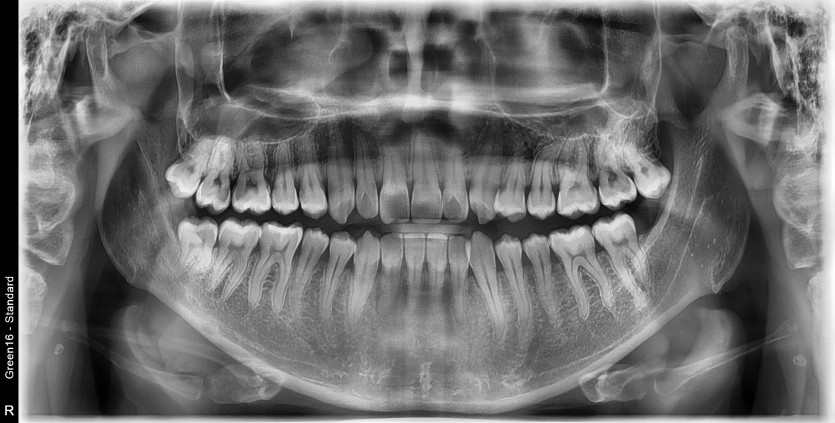

#18,28,48 사랑니 발치

구강 외과 전문의가 당일 발치했습니다.